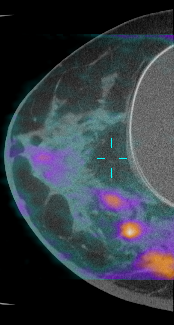

TC de Seno Dedicada: La investigación financiada por el NIBIB ha llevado al desarrollo de un escáner de TC de seno dedicado (dbCT por sus siglas en inglés) que permite a los radiólogos ver el seno en tres dimensiones y tiene el potencial de revelar pequeños tumores oscurecidos detrás del tejido denso del seno. El escáner utiliza una dosis de radiación comparable a la mamografía al enviar rayos X solamente a través del seno y no del pecho. Actualmente, más de 600 mujeres han sido examinadas con la dbCT en ensayos clínicos. Los resultados de estos ensayos sugieren que la dbCT es considerablemente mejor para detectar tumores que la mamografía, aunque la mamografía es mejor para detectar microcalcificaciones. Recientemente, la tecnología de tomografía por emisión de positrones (PET por sus siglas en inglés) se ha incorporado a la plataforma de la dbCT. Una tomografía PET resalta las áreas de mayor actividad metabólica, lo que podría indicar la presencia de un tumor. Además, la inyección de un medio de contraste ha demostrado que mejora la habilidad de la dbCT para detectar microcalcificaciones y podría ayudar a los radiólogos a distinguir entre tumores malignos y benignos. Actualmente la investigación está enfocada en las maneras en que podría usarse la dbCT para proveer una guía de imágenes en tiempo real para la colocación de la aguja de biopsia y la ablación mínimamente invasiva de los tumores. Para mayor información sobre la dbCT, haga clic aquí.